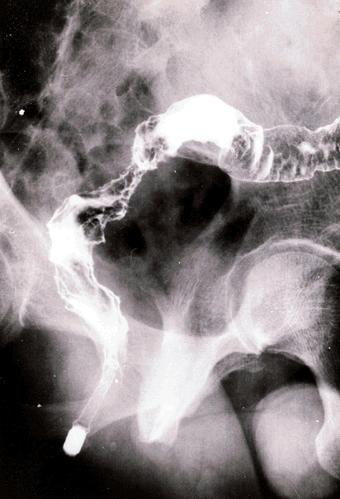

疾患(病理主体)の分類悪性上皮性腫瘍/腺癌

部位(臓器別)大腸/直腸

検査方法X-P

腫瘍の肉眼分類4型(びまん浸潤型)/

病変の最大径(ミリ)40以上